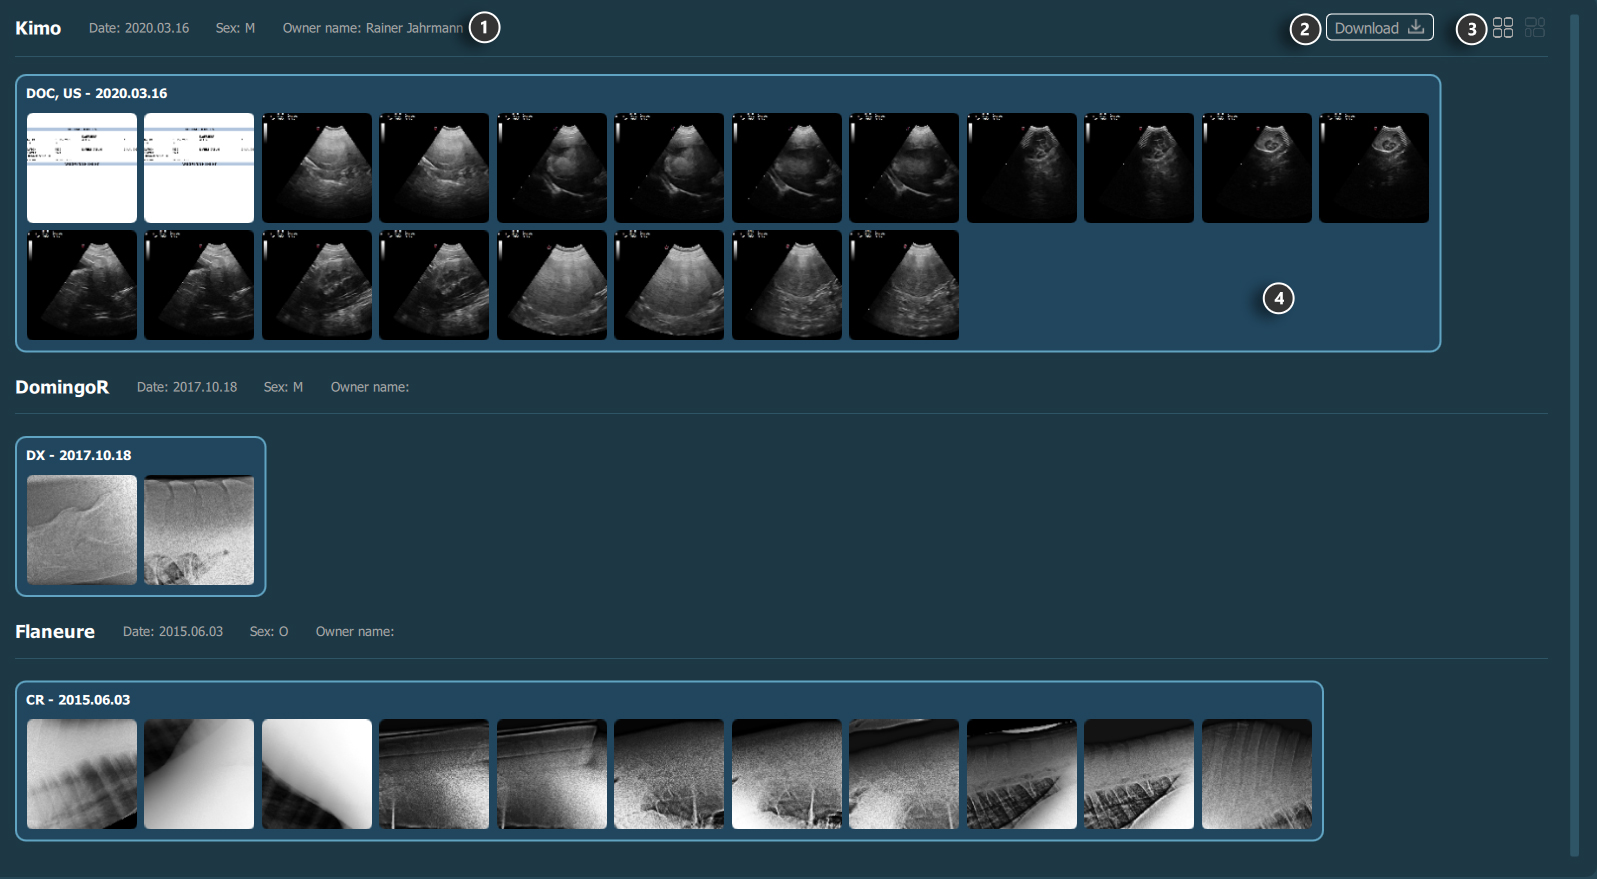

Preview Pane / Home Screen¶

Patient information

Download selected studies’ image data (optional)

Thumbnail image aspect ratio (unified/original)

Study preview